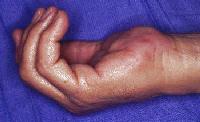

Clinical Example: Reactive fibroosseous pseudotumor of the palm

Reactive fibroosseous pseudotumor may resemble a soft tissue malignancy, but is a benign process, similar to myositis ossificans.

This rubbery hard mass developed over the course of a year. There was a history of some repeated impact to the area.